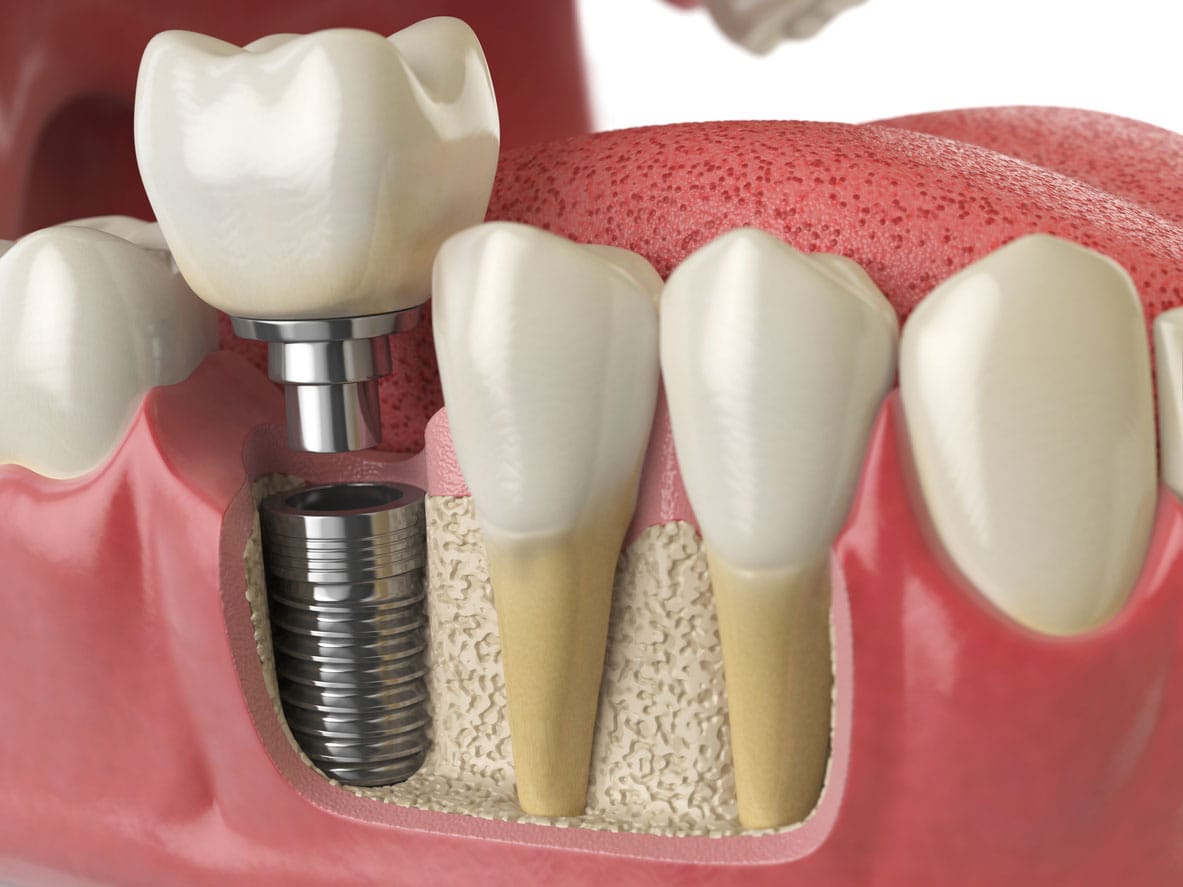

Dental implants are a modern, long-term solution for replacing missing teeth that look, feel, and function like natural teeth. They consist of a biocompatible titanium post that is placed into the jawbone, acting as an artificial tooth root, over which a custom-made crown, bridge, or denture is fixed. Implants help restore chewing efficiency, speech, and confidence while also preventing bone loss and maintaining facial structure. With proper planning, advanced technology, and good oral hygiene, dental implants offer a highly predictable, durable, and aesthetically pleasing option for patients seeking a permanent replacement for missing teeth. Dental implants, dental implant treatment, best dental implants, tooth replacement options, missing teeth solution, permanent tooth replacement, implant dentist near me, dental implant clinic, titanium dental implants, single tooth implant, multiple teeth implants, full mouth dental implants, all-on-4 dental implants, implant-supported dentures, painless dental implants, advanced implant dentistry, affordable dental implants, long-lasting tooth replacement, natural-looking dental implants, smile restoration, bone loss prevention, modern dental implant technology, implant consultation, dental implant cost, and post-implant care are some of the most searched terms related to dental implants and are commonly used by patients looking for a safe, reliable, and permanent solution for missing teeth. We are one stop solution for all your dental problems. Together we make you smile. Consult us now. Contact us at 7259693009. Dentist near me, Best dental clinic in Bangalore, smile dental clinic, Orthodontic center Bangalore, Orthodontic center in BTM Jayanagar HSR, Top 10 dental clinic in Bangalore, Best dental clinic is BTM HSR Jayanagar, Invisalign, Invisalign clear aligners, Invisalign treatment, Invisalign treatment in Bangalore, Braces in Bangalore, Braces in BTM Jayanagar HSR, Invisalign in South of Bangalore.